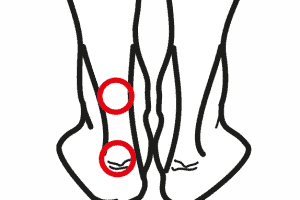

Gonartrosi femoro tibiale

Il ginocchio è una struttura complessa e fondamentale del nostro corpo. Collega la coscia e la gamba, permettendoci di muoverci liberamente. La cartilagine articolare svolge un ruolo primario in quest’area, proteggendo e ammortizzando le ossa degli arti inferiori durante i movimenti. La struttura anatomica del ginocchio Il ginocchio si compone di due articolazioni principali: la prima … Continued